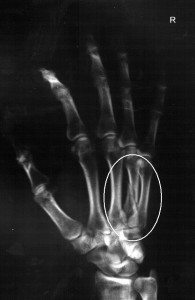

Kırıklarda en önemli belirti, kırılan kemiğin olduğu bölgede çok şiddetli bir ağrı olmasıdır. Kişinin hissettiği acı bazen dayanma gücünü zorlayacak düzeyde olabilirken, kemiğin pozisyon değiştirmemesi yani halk arasında bilindiği gibi çatlak olması halinde bu acının daha düşük seviye olması da mümkündür. Ancak unutulmamalıdır ki, bazen kemik kırılmış olmasına karşın kişi ilk aşamada çok şiddetli ve dayanılmaz bir acı hissetmeyebilir. Bu nedenle kırıkların anlaşılması için kulaktan dolma bilgilere değil, mutlaka uzman bir hekimin muayenesine güvenmek gerekir. Kırıklar kemiğin iki parçaya bölünmesine sebep olurken çatlaklar sadece bir yüzeyde kırılma yaşanmasına ve bu nedenle tek parça kalan kemiğin daha az ağrıya sebebiyet vermesine neden olabilir. Ayrıca kırılan bölgede şişlik ve geçen zaman için morarma yaşanması da söz konusu olabilir.

Kırıkların anlaşılması için birçok kapsamlı tıbbi tahkik yapılması gerektiğinden en ufak bir şüphe olmasına dahi uzman bir doktora danışılması gerekir. Bu nedenle yalan yanlış bilgilerle bireysel saptama ve en önemlisi de tedavi uygulamalarına yönelmemek, belki de akıldan çıkarılmaması gereken en önemli konudur. Zira kemiğin yapısının bozulmasına sebep olan kırıklar çok farklı şekillerde gelişebilmekte ve bu tür yanlışlar ilerleyen aşamada tahmin edilemeyecek kadar ciddi sağlık sorunlarına sebebiyet verebilmektedir.